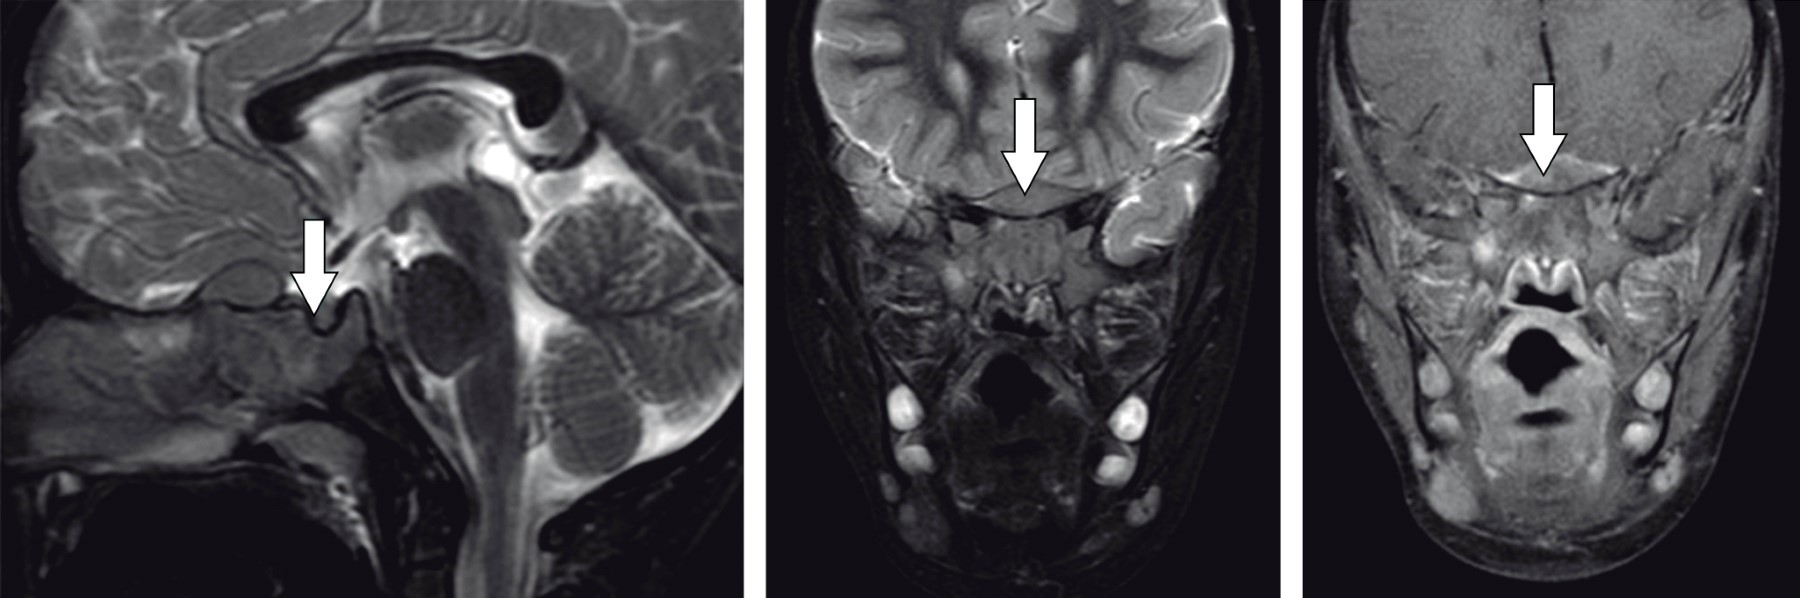

El servicio de oftalmología confirma oftalmoplejía completa del ojo derecho, con probable alteración de los pares craneales III, IV y VI. Pero la agudeza visual y fondo de ojo se consideraron normales. Por lo anterior, se decide realización de tomografía de cráneo y órbitas con medio de contraste, la cual mostró una lesión ósea esfenoidal con componente de partes blandas intracraneal. Se consideró diagnóstico de linfoma, pero se tenían que descartar otros diagnósticos como rabdomiosarcoma, histiocitosis de células de Langerhans o metástasis de neuroblastoma. Tres días después se efectúa resonancia magnética (RM) de cráneo, que apunta hacia la misma hipótesis diagnóstica (Figura 1). Por los hallazgos en estudios de imagen de una lesión muy probablemente de origen tumoral en seno esfenoidal se realizó biopsia, mediante abordaje endoscópico transetmoidal.

Figura 1